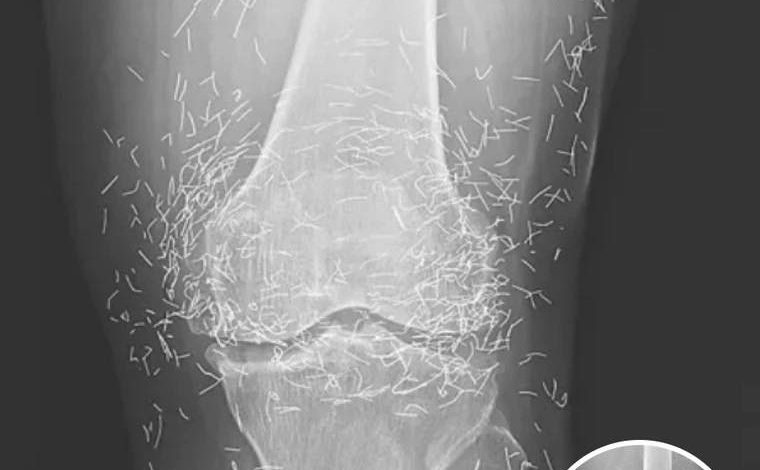

Doctors Stunned After Looking At This X-Ray Of Woman Suffering Joint Pain

A routine X-ray revealed an unexpected surprise when doctors examined the knees of a 65-year-old woman suffering from severe joint pain. What they found was nothing short of astonishing — hundreds of tiny gold needles embedded deep in her tissue.

A X-ray of the patient’s knee showing acupuncture needles embedded in the tissue, Photo Credit: Reddit

As for the South Korean woman, her case was recently documented in the New England Journal of Medicine. While the needles may have been intended to help, her X-rays tell a cautionary tale about the potential risks of extreme alternative therapies.